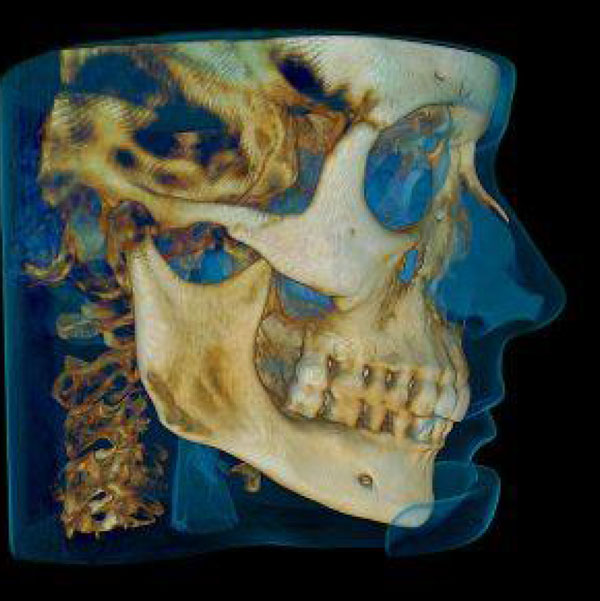

3D Digital CT scanner by Carestream:

Get the most advanced x-rays in the state with a digital 3D Cone Beam at Flat Rate Doctors! We are proud to be one of the few offices in the state of Utah to offer 3D Cone Beams to our patients. CT images can be used to help with wisdom teeth extractions, placement of implants and a wide array of dental treatments along with use for our chiropractic services for cervical neck x-rays.

Latest Technology and Training

Our Flat Rate dental team has considerable training and experience placing dental implants. By utilizing the latest technology, such as our 3D CT scanner, and procedures we can place dental implants efficiently and with minimal discomfort. Our partner dentist is a diplomat in dental implantology and teaches how to place implants with years of experience.